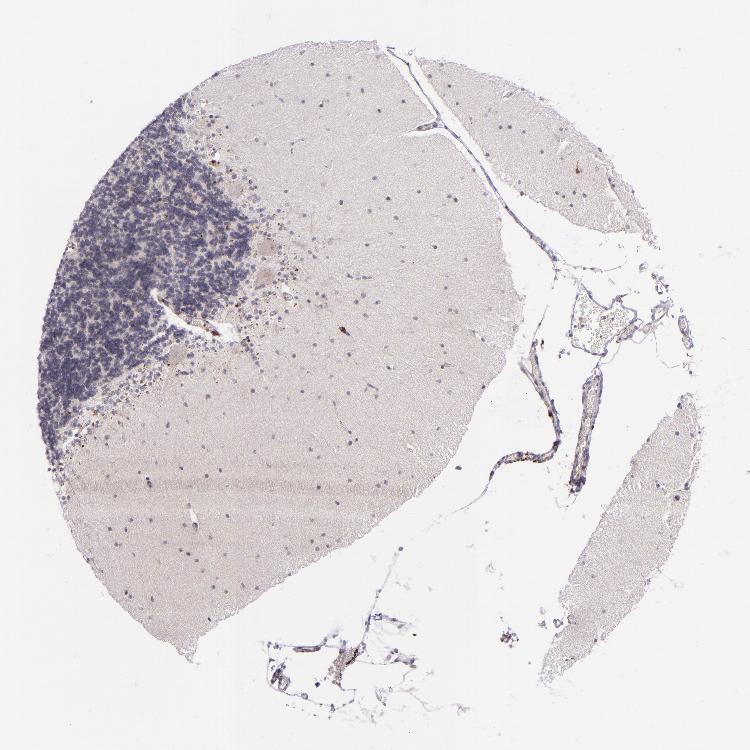

CEREBELLUM - Antibody stainingi

Antibody staining in the annotated cell types in the current human tissue is reported as not detected, low, medium, or high, based on conventional immunohistochemistry profiling in selected tissues. This score is based on the combination of the staining intensity and fraction of stained cells.

Each image is clickable and will lead to virtual microscopy that enables deeper exploration of all samples and also displays staining intensity scores, fraction scores and subcellular localization as well as patient and tissue information for each sample.

Antibody CAB002144

Purkinje cells Not detected

Cells in granular layer Not detected

Cells in molecular layer Not detected